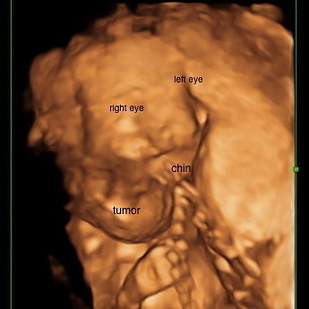

Three weeks later, Paradiso got an MRI that confirmed their worst fears: The tumor had tripled in size and was growing into her head, chest, lungs, and eyes. It was inoperable.

However, doctors learned from the MRI that Omara’s case was far worse, and the tumor was growing inside her brain as well. “It was aggressive lymphangioma, and it was three times the size of her head by now and they were 99% sure it was fatal,” Paradiso said.

“When she was born and we could see the extent of the tumor, we were shocked,” Paradiso said.

“To give more context, when we took the picture (above) where you can see her tumor, it had already been drained and reduced in size,” Paradiso said.